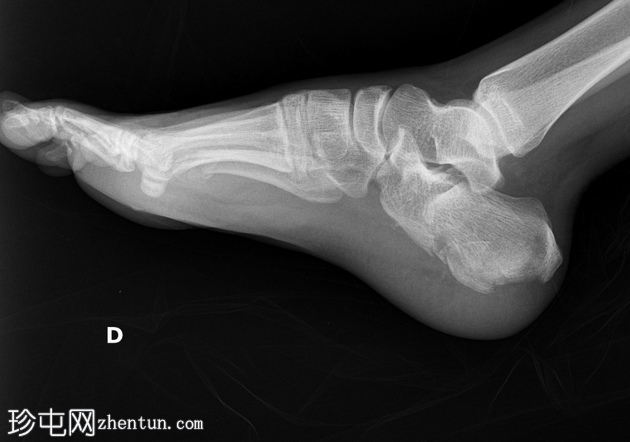

4.png

正位(放大)

第四趾近节指间关节(PIPJ)跖侧脱位。

第五趾近节指骨无移位骨折。

第五跖骨颈骨折伴跖侧移位(背侧成角)。

跟骨关节内骨折。

跟骨骨折患者常伴有其他肌肉骨骼损伤,其中最重要的是:胸腰椎骨折、对侧跟骨骨折以及同侧下肢其他部位骨折。本例患者存在:近端指间关节脱位、趾骨骨折、跖骨骨折以及AO C型L3椎体骨折(本研究中未显示)。